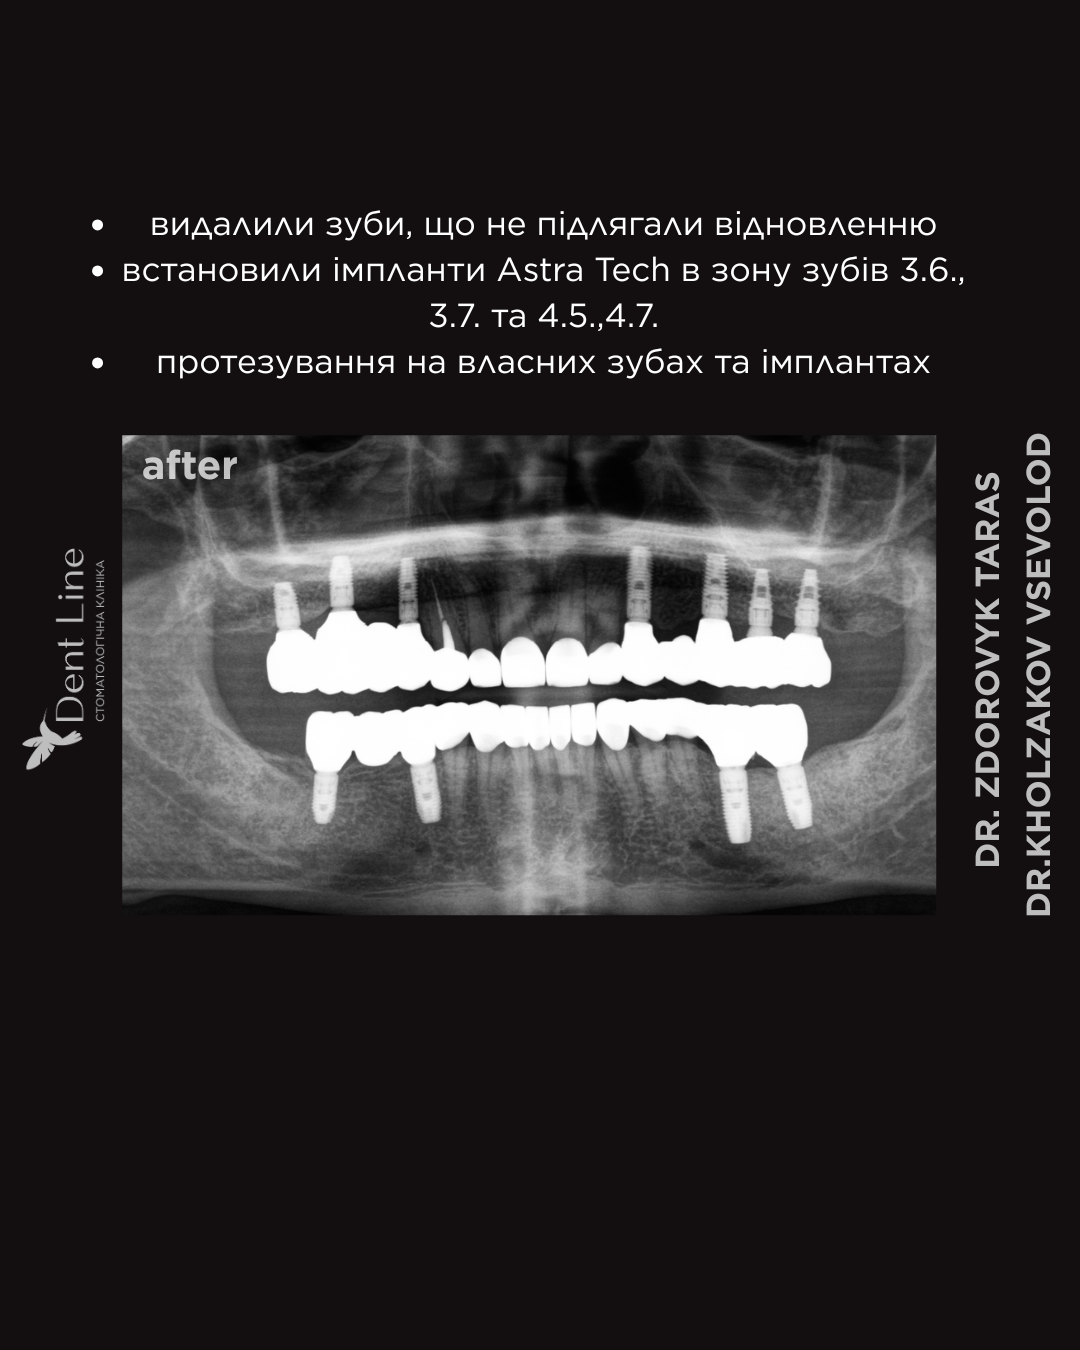

- Видалення зубів, які не підлягали відновленню;

- Встановлення імплантів Astra Tech у зону відсутніх зубів 3.6., 3.7. та 4.5.,4.7.;

- Протезування як на власних зубах, так і на імплантах;